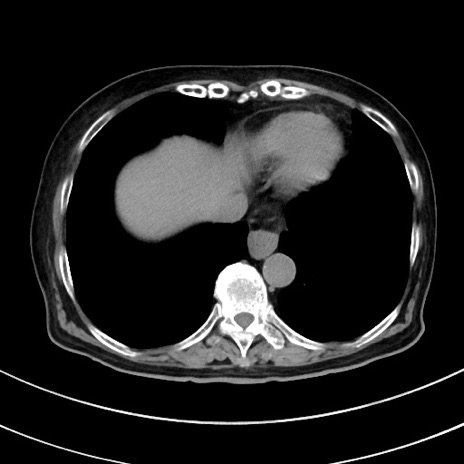

症例33(横断像)

【症例】70歳代 女性

【主訴】心窩部痛

【現病歴】延髄病変の精査・加療にて神経内科入院中。本日より心窩部痛あり。

【身体所見】右下腹部を中心に圧痛と反跳痛あり。